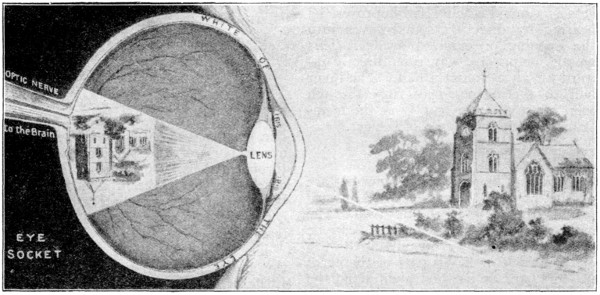

Picture Diagrams of Eye and Ear